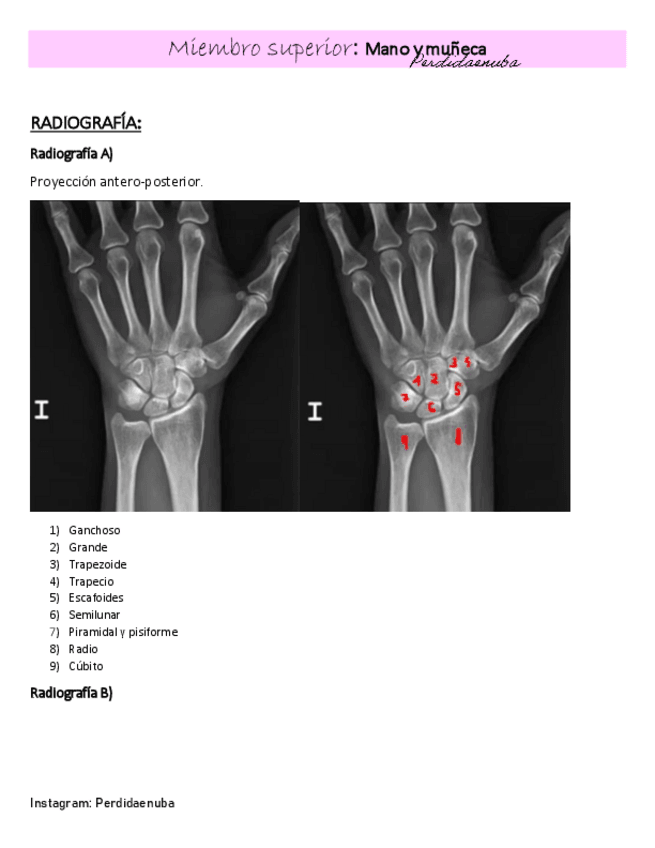

He publicado nuevos apuntes de 8º Cirugía General: MANO-Y-MUNECA.pdf